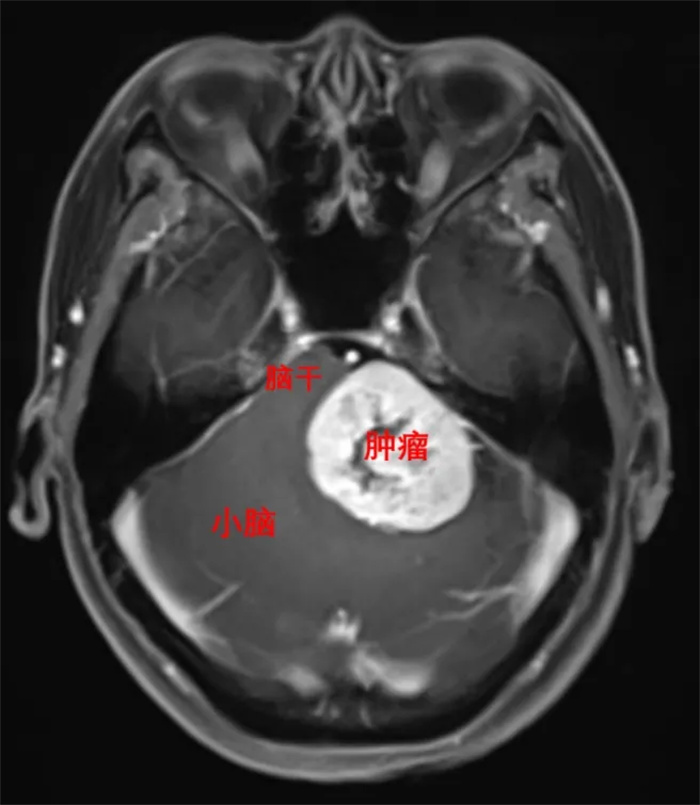

2024-12-30孕34周產(chǎn)婦顱內(nèi)有大腫瘤?順德這個(gè)“拆彈”團(tuán)隊(duì)出動(dòng)了

近日,陳先生夫婦將一面寫有“杏苑仁心 妙手回春”的錦旗,送到了我院神經(jīng)外科團(tuán)隊(duì)的手中,回想一個(gè)月前動(dòng)魄驚心的經(jīng)歷,他們依舊心有余悸,但所幸結(jié)果有驚無險(xiǎn),平穩(wěn)度過。閱讀全文